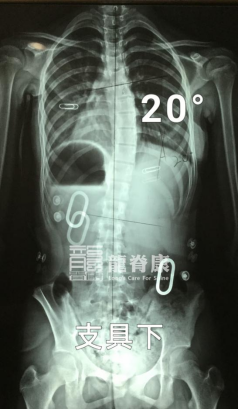

孩子佩戴支具下的度数

在最初的一年里,小墨坚持每3个月回来复查体态以及调整支具。3个月复查时,脱支具4小时后的X光片显示,她的胸弯度数已经从50°减至39°,且剃刀背都有明显改善,右背部剃刀背由14°减至7°,左腰部剃刀背由12°减至8°。